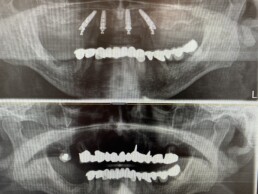

Wie läuft das eigentlich mit All-on-4 ab? Diese Frage ist eine sehr häufige Frage, und die Antwort ist aber auch sehr einfach. Hier im Video kurz und einfach erklärt. Am wichtigsten ist das Kennenlernen des Patienten bei der ersten Beratung, ob dieses Konzept der festen Zähne an nur einem Tag mit 4 Zahnimplantaten ( es gibt ja auch viele andere Konzepte) für den jeweiligen Patienten überhaupt in Frage kommt, ob der Kiefer dafür geeignet ist. Dazu muss einfach ein 3D-Röntgen gemacht werden, um festzustellen, ob der Knochen in Qualität und Menge dafür in Frage kommt. Falls ja, bekommt der Patient einen exakten Heilkostenplan mit Fixpreisgarantie. Bei Zusage wird beim zweiten Termin mit der Anfertigung des späteren Zahnersatzes begonnen. Beim 3. Termin erfolgt bereits der Eingriff, entweder in lokaler Betäubung oder auch in Narkose. Beim 4. Termin wird bereits der Zahnersatz auf die Implantate geschraubt. Und das wars!